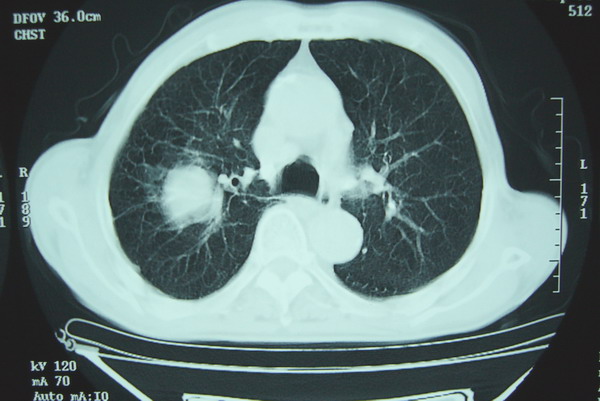

标题: CT15579:男 86岁 咳嗽 咳少量白痰 发热2天 吸烟史60年 [打印本页]

标题: CT15579:男 86岁 咳嗽 咳少量白痰 发热2天 吸烟史60年

右上周围型肺癌,慢支,肺气肿。

分叶及少量边缘性钙化,老年人,周围性肺癌首先考虑。

右上肺一不规则团块,边缘有分叶和毛刺,纵隔有淋巴结肿大。右肺周围性肺癌首先考虑。